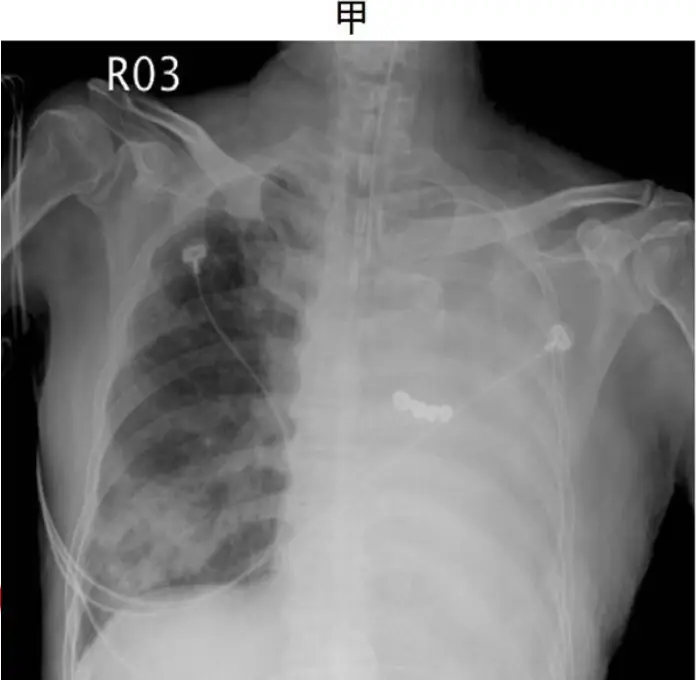

病人甲與病人乙皆主訴左胸悶、呼吸喘促,其胸部 X 光發現兩人的左胸廓都幾乎全白,如圖(三)。如果單以 X 光判讀來決定,是否適合為病人進行胸管引流來減輕其症狀,請問下列何項決策正確?

- 病人甲(A):左側幾乎全白,但可見肺紋理向外延伸,肺容積大致未見顯著縮小,無縱隔或氣管明顯偏移;符合肺實質被炎性分泌物充滿,也常見 air bronchogram,與嚴重 pneumonia/consolidation 相符,並非 pleural fluid (pmc.ncbi.nlm.nih.gov)。